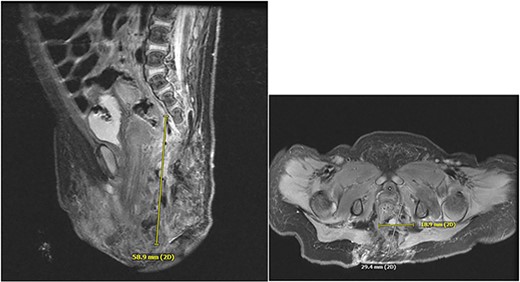

A 3-week-old girl born at 39 weeks, 1 day gestation with a left buttock hemangioma presented to the emergency department with progressive deterioration of the skin of the left buttock, wrapping laterally around the thigh and extending to the labia. She first developed ulceration at 1 week old after receiving silver nitrate treatment for IH at an outside facility. This progressed over 2 weeks to its state upon presentation, involving the left buttock, perianal region, and labia, growing in both size and depth (Fig. 1). On admission, ulceration was managed with broad spectrum IV antibiotics: vancomycin, clindamycin, and cefepime. CT and MRI revealed a 5.9 cm vascular mass with intrapelvic and extrapelvic components and spinal dysraphism from L4 to the sacrum along with spinal cord tethering due to an intradural lipoma, consistent with LUMBAR syndrome (Fig. 2). The patient had involvement on the dorsum of the left foot, consistent with IH (Fig. 3).

Deep, erythematous perianal ulcerations extending into the labia with peripheral vascular papules, consistent with IH.